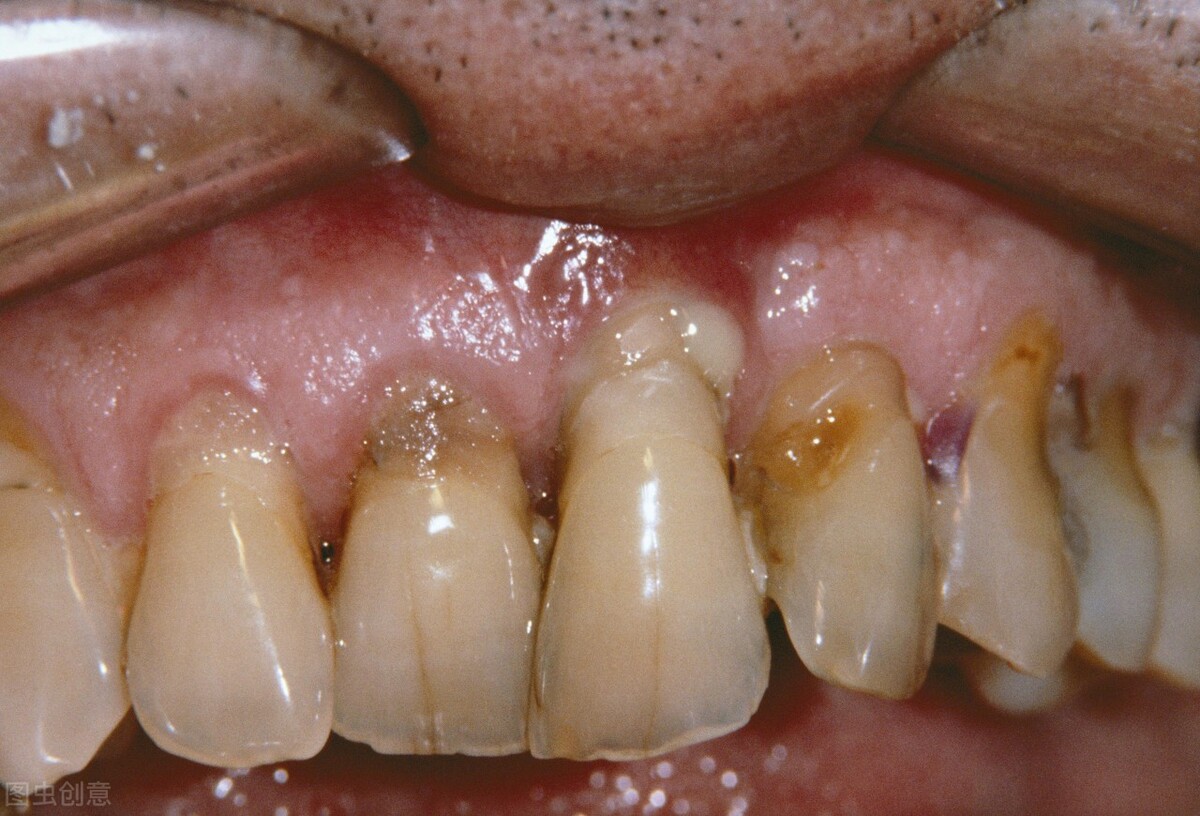

1、血液性疾病

牙龈容易出血,且出血不止,不容易止血的情况就要警惕是否存在血液性疾病了。

3、糖尿病

虽然糖尿病本身不是引起牙周炎的关键,但是患有糖尿病的患者更容易出现牙周病并且更易加重牙周炎的症状,同时牙周炎也容易增加糖尿病的并发症糖尿病肾病和心血管疾病的风险。